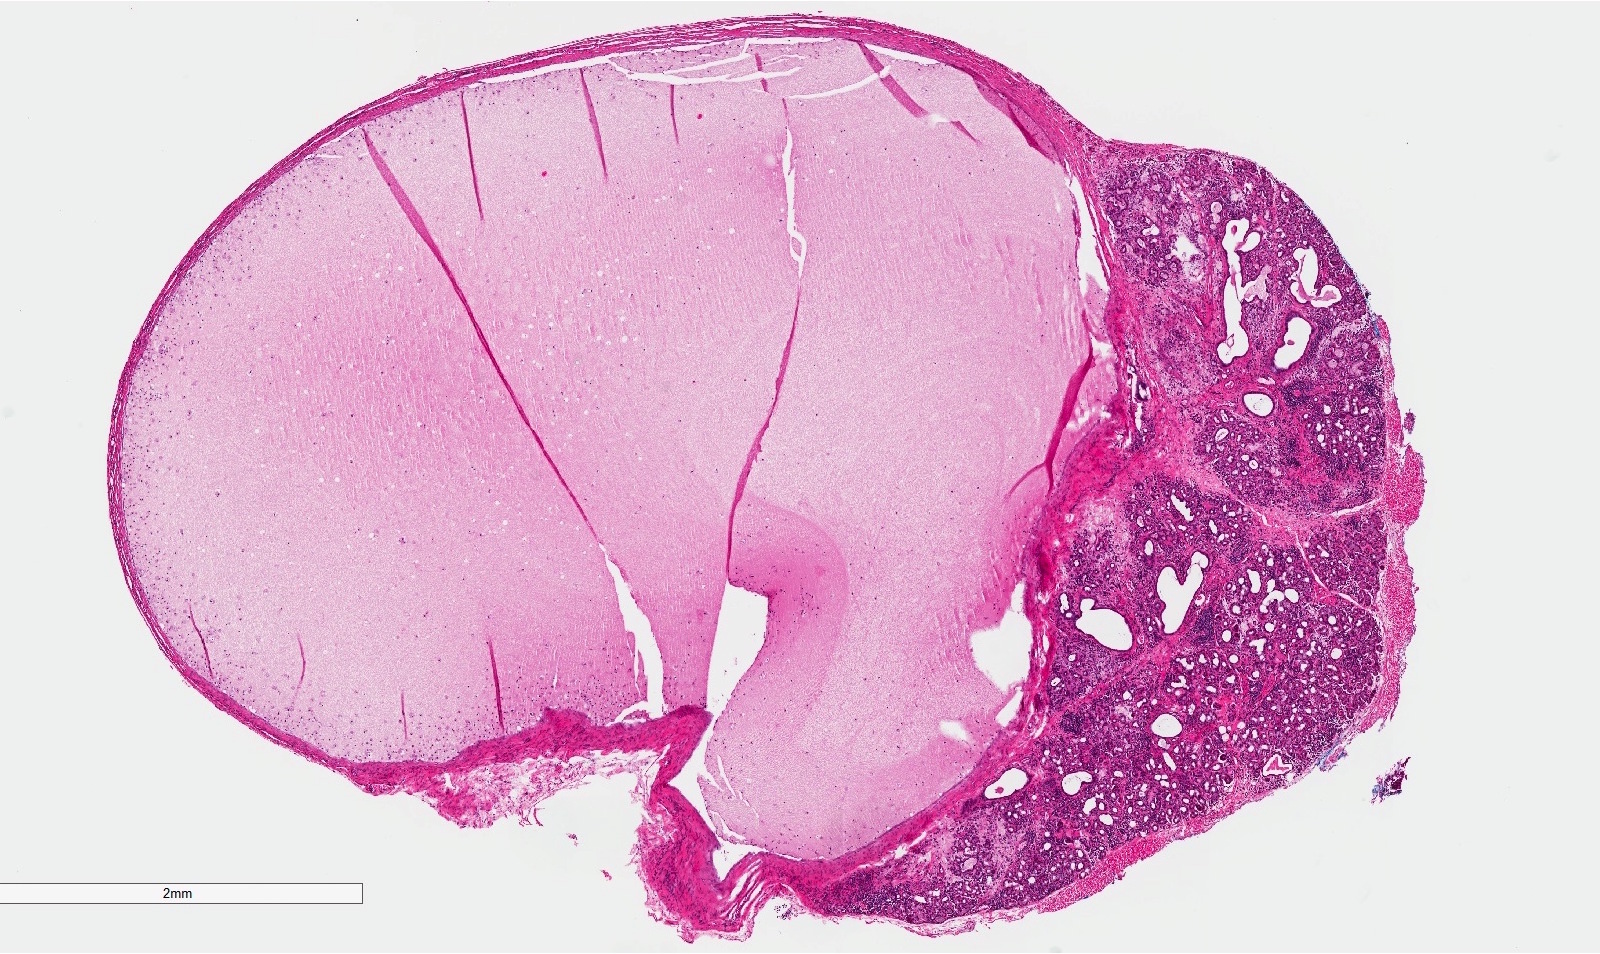

Microscopic (histologic) description

- If removed intact

- Pseudocyst cavity containing mucin, abundant epithelioid foamy histiocytes (muciphages), neutrophils and granulation tissue (Acta Histochem 2014;116:40)

- If removed ruptured

- Fragments of granulation tissue containing epithelioid foamy histiocytes (muciphages) and neutrophils, may see mucinous material (Acta Histochem 2014;116:40)

- Removed salivary gland parenchyma showing obstructive changes

- Acinar atrophy, ductal dilatation with periductal hyalinization, interstitial lymphoplasmacytic infiltrate and interstitial fibrosis at late stage (J Oral Maxillofac Surg 2008;66:2050)

- May see ruptured feeding salivary duct with squamous metaplasia (J Oral Maxillofac Surg 2008;66:2050)

- Long standing lesions organize into fibrosis resembling a fibroepithelial polyp (Acta Histochem 2014;116:40)

- No epithelial cyst lining, may see overlying surface oral mucosa with variable atrophy in superficial mucoceles (J Oral Maxillofac Surg 2011;69:1086)

Microscopic (histologic) images